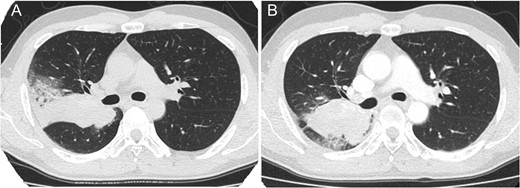

Thirteen years after the first treatment, the patient presented to our institution because of a lung mass detected during a medical checkup. Computed tomography (CT) showed a 76 × 38 mm2 mass in the right lung (Fig. 1A); no other tumor was detected. The alpha-1 fetoprotein (AFP), beta-subunit of human choriongonadotropin (βHCG) and human choriongonadotropin (HCG) levels were 154.2 ng/mL, <0.1 ng/mL and <1.0 mIU/mL, respectively. Late relapse of testicular cancer was highly suspected. After three cycles of GCT-oriented chemotherapy CT showed that the tumor had increased in size (Fig. 1B). He received a pneumonectomy. Pathology showed a well-differentiated adenocarcinoma (Fig. 2A) with immature teratoma (Fig. 2B). The patient was diagnosed with testicular tumor/teratoma with SM. The patient has experienced no relapse for 9 years after pneumonectomy to date.

Thoracic computed tomography showing lung tumor before chemotherapy (A) and after chemotherapy (B) in case 1. The tumor increased in size after chemotherapy.